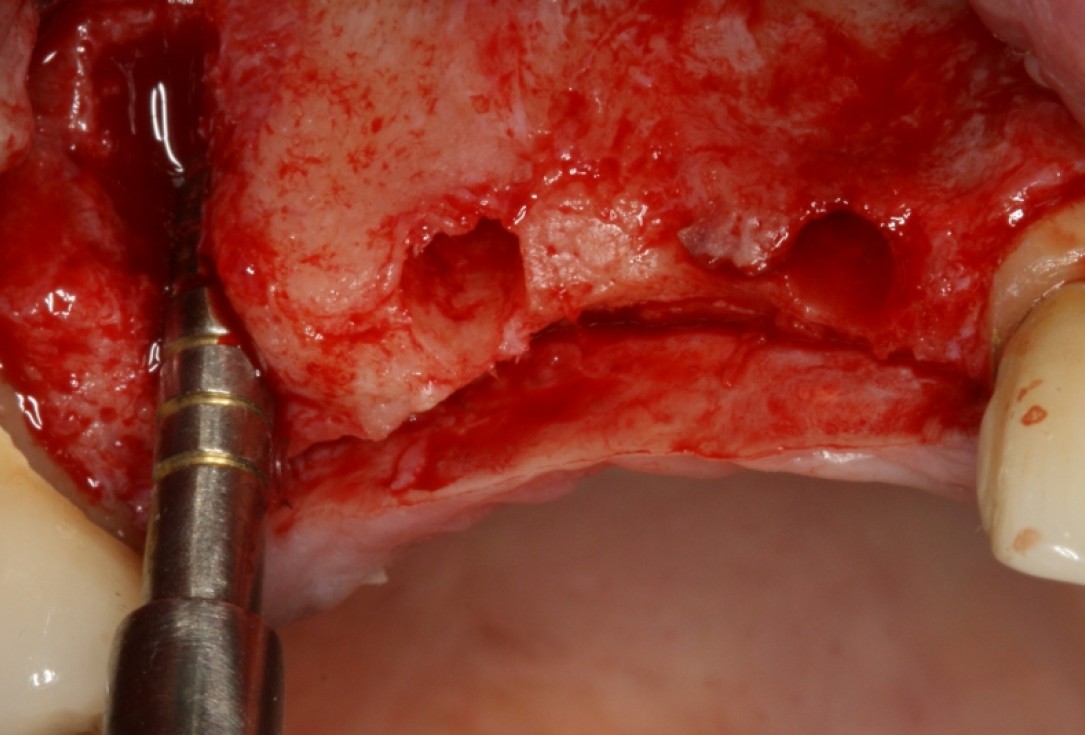

botiss cerabone® & Jason® membrane for GBR - Clinical case by Dr. S. Kovalevsky

Implant insertion in atrophic alveolar ridge